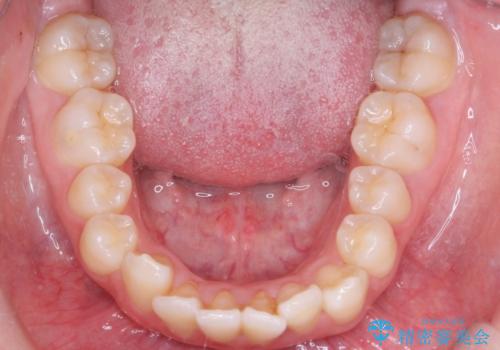

- 八重歯を主訴に来院されました。

左側犬歯が埋伏していましたが、第一小臼歯(4番目の歯)を抜歯したことでできたスペースに牽引し、右側の飛び出した八重歯を含め、歯全体を整列することができ患者様も満足していただきました。